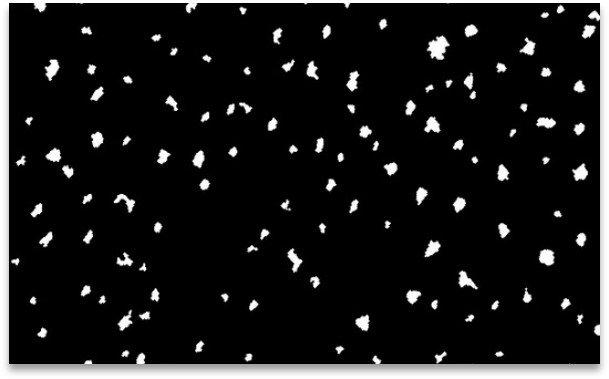

In 2D, this involves color analysis, followed by shape identification to eliminate other objects and retain only the pores. The results are images processed in black and white. You also get a spreadsheet with the median area, median diameter and pore density of each image.

Source image Processed image